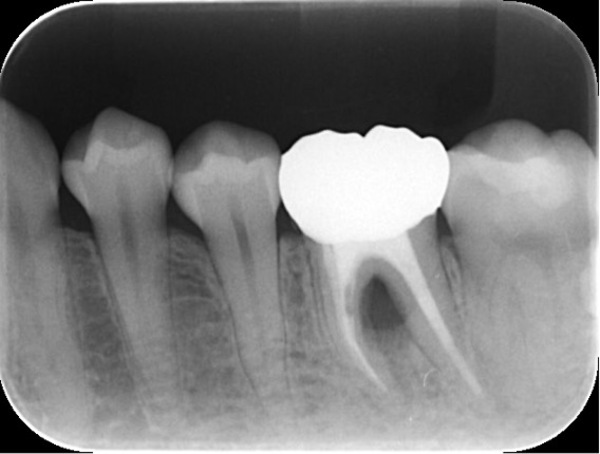

こちらが初診時のX線写真です。

X線で左下6番周囲の骨が明らかに欠損していることがわかります。この段階で神経が壊死している(歯髄失活)可能性、歯周病の可能性などが考えられ、様々な検査を行いました。

検査の結果、痛みの原因は主に歯髄失活によるものだと考えられました。結果として、大きく骨を破壊され、軽度の歯周病の病変と繋がっているという診断となりました。